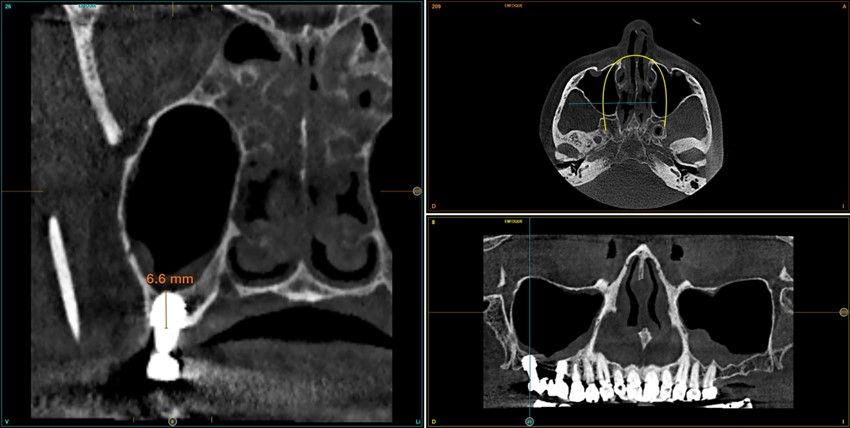

Resultados. Fueron reclutados 13 pacientes en los que se insertaron 30 implantes. Una vez insertados y cargados los implantes, la altura media final fue de 9,68 mm (+/- 2,66), lo que supone una ganancia promedio de 5 mm. A los 10 años, se observó una disminución media de la altura ósea ganada en los implantes en conjunto de 0, 29 mm (+/- 0,77). La media de la pérdida ósea mesial fue de 0,73 mm (+/- 0,75 mm) y la media de la pérdida ósea distal fue de 0,98 mm (+/- 1,2 mm). La supervivencia fue del 100%.

Results.Thirteen patients were recruited and 30 implants were inserted. Once the implants were inserted and loaded, the mean final height was 9.68 mm (+/- 2.66), which represents an average gain of 5 mm. At 10 years, there was a mean decrease in the overall bone height gain of the implants of 0.29 mm (+/- 0.77). The mean mesial bone loss was 0.73 mm (+/- 0.75 mm) and the mean distal bone loss was 0.98 mm (+/- 1.2 mm). Survival was 100%.

Nuestro grupo de estudio modifica esta técnica de elevación transcrestal utilizando para el acceso unas fresas de corte frontal que permiten eliminar la cortical inferior del seno con lentitud sin dañar la membrana de Schneider, eliminándose los osteotomos y el malestar que genera su accionamiento mediante el martillo6-7. Inicialmente el procedimiento fue concebido para ser empleado con material de injerto al igual que el abordaje convencional, pero posteriormente se presentaron variaciones del procedimiento donde se insertaban los implantes sin injerto, utilizándose el propio implante como mantenedor de espacio entre la membrana de Schneider y la cavidad creada entre la membrana y la cresta, permitiendo que esta cavidad no se colapsase y posteriormente fuera colonizada por nuevo hueso7-11.

Los senos tratados con la técnica de elevación transcrestal sin material de relleno muestran un incremento de entre 2,5 mm12,13 hasta 4.4 mm14,15 en la altura ósea lograda sobre el ápice y una supervivencia de los implantes que se sitúa entre un 94 y un 100%16-17. En este trabajo se presenta un estudio retrospectivo donde se ha evaluado la inserción de implantes extracortos (5,5 y 6,5 mm) en zonas posteriores maxilares mediante la técnica de elevación de seno transcrestal con la fresa de ataque frontal sin la utilización de material de injerto, con un tiempo de seguimiento de 10 años para poder objetivar el comportamiento de los implantes a largo plazo y de la técnica empleada.